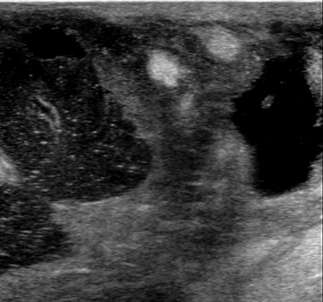

Hypoechoic mass with indistinct margins

The above ultrasound demonstrates a hypoechoic (dark) mass with indistinct margins, posterior shadowing, and distortion of the normal breast tissue. This was biopsied, revealing invasive ductal carcinoma (IDC). Both ductal carcinoma in situ (DCIS) and IDC may result in distortion.